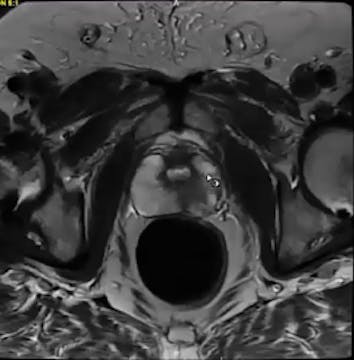

Gleason score, active surveillance, periodic biopsy, prostate gland, pelvis, SIB, radiation-induced fibrosis, brachial plexus, head and neck, scleroderma, SBRT, TNM staging, bladder cancer, ASTRO, PSMA PET imaging, salvage prostatectomy, PSA

urethral tumor, urothelial carcinoma, PET, CT, palliative treatment, mediastinal nodes, biopsy, prostate gland, PSMA, false positive, pelvis with nodes, bone lesions, PSA, bladder